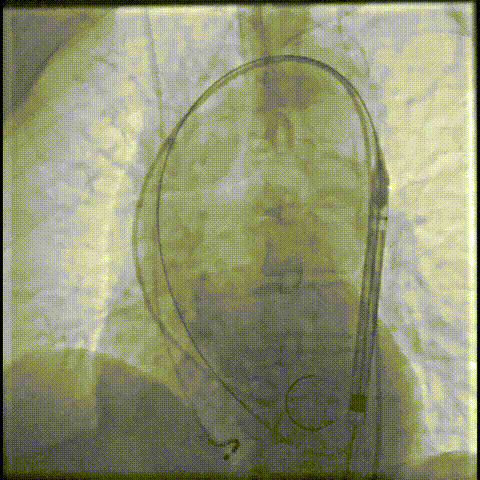

器械过弓柔顺

轻松过弓,精准可控:该病例弓角小,在未使用snare的情况下,轻松完成过弓,通过性能得到了很好的验证;